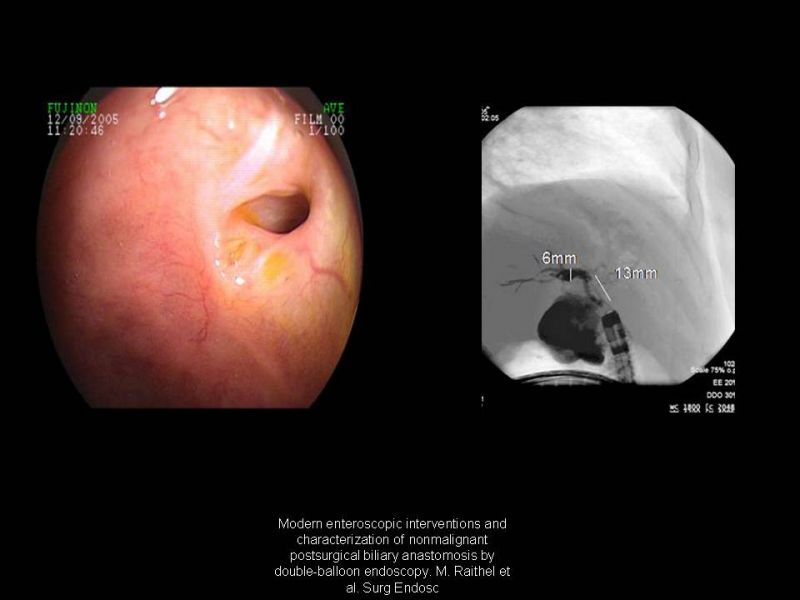

Estenosis de anastomosis biliodigestivas

Hepatobiliopancreático

| Autor: Dr. Julio Nuñez V.